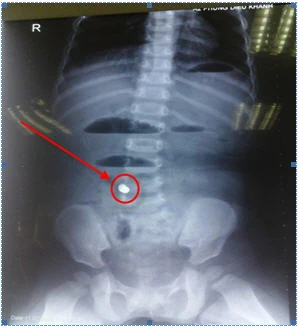

Phim chụp X-Quang cho thấy có dị vật trong bụng trẻ. Ảnh: BS cung cấp

Qua thăm khám và chụp X-quang, siêu âm bụng, các BS phát hiện có hình ảnh của dị vật trong bụng của trẻ, chẩn đoán tắc ruột do nuốt phải dị vật. Trẻ được mổ nội soi cấp cứu. Kết quả tìm thấy có đoạn ruột giãn và đoạn ruột xẹp (ranh giới chỗ tắc ruột), tại ranh giới này thấy có dị vật hình trụ đường kính 0.5cm, dài 1 cm gây viêm hoại tử thành ruột lộ ra ngoài, dính với mạc treo tạo đọan gập góc gây tắc ruột. Các BS đã tiến hành mở rộng vết mổ tại rốn (khoảng 2cm), đưa đoạn ruột tổn thương ra ngoài, cắt đoạn ruột bị tổn thương có chứa dị vật khoảng 5 cm (có 4 dị vật dính với nhau), nối lại ruột. Theo các BS, dị vật này chính là bốn hạt kim loại có từ tính giống như nam châm, có khả năng hút nhau.